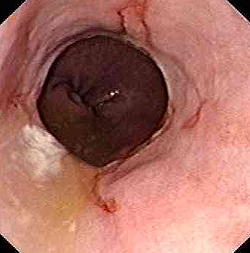

Вирусный эзофагит.

При компьютерной томографии определяется утолщение стенки пищевода более 5 мм со значительным утолщением складок слизистой оболочки (стрелки)